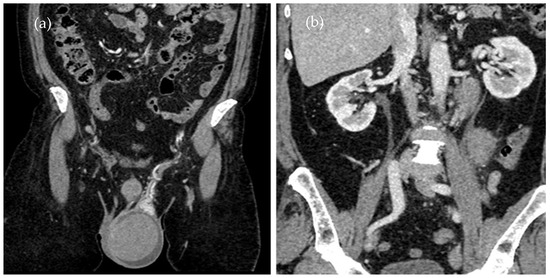

Testicular ultrasound showed an enlarged left testicle of approx. 63/55 mm (Figure 2a), with inhomogeneous diffuse infiltrated echo structure and alternating hypoechoic areas, vascularized in Doppler and B-Flow (Figure 2b), without specific intraparenchymal masses detectable by ultrasound. Transonic peri-testicular fluid was approx. 7 mm diameter (Figure 2c).

Figure 2. Axial ultrasound section of the left testicle: (a) increased volume, inhomogeneous echo structure, alternating hypoechoic areas; (b) vascular signal present in Doppler; (c) vascular signal present in B-Flow.